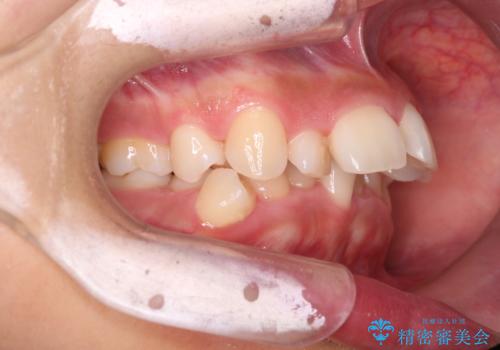

- 前歯の凸凹を主訴に来院されました。

抜歯を行い、ワイヤー矯正にて治療を行いました。

CTにて骨を確認し、側切歯の歯根をこれ以上頬側に出せないことを確認しています。